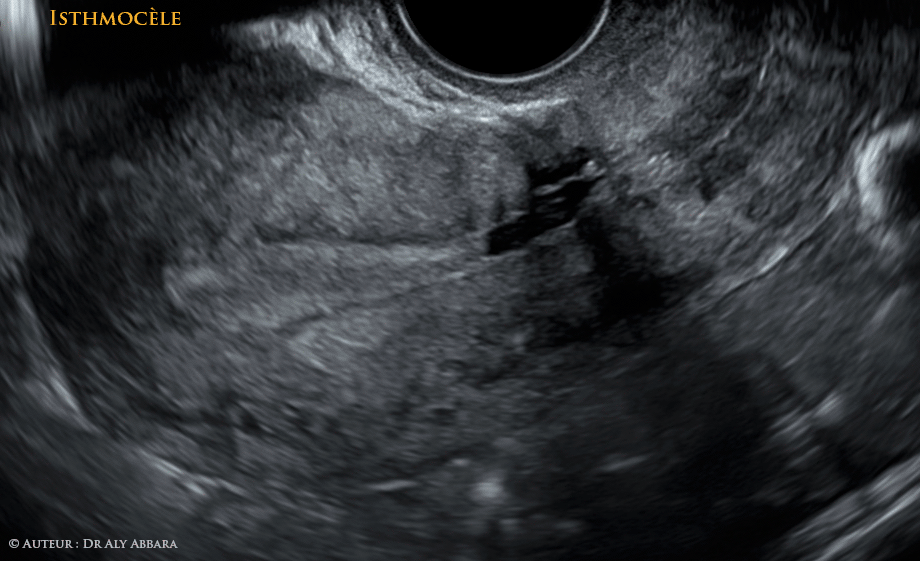

- Séquence vidéo et image animée montrant un des aspects de l'isthmocèle, c'est-à-dire une déhiscence secondaire à un défaut de cicatrisation de la cicatrice de l'hystérotomie segmentaire transversale réalisée lors de la césarienne.

- A comparer à l'aspect habituel d'une cicatrice de césarienne non compliquée d'une isthmocèle.

Il s'agit d'une déhiscence de la cicatrice d'hystérotomie de la césarienne secondaire à un défaut de cicatrisation.